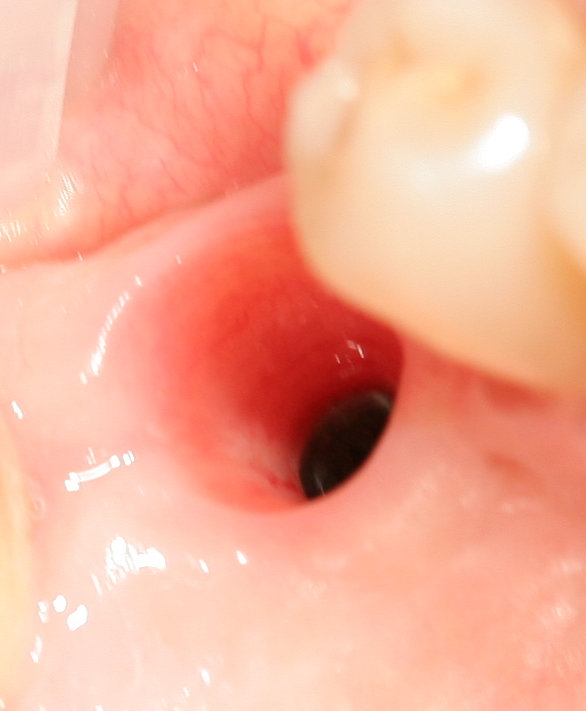

На увеличенных фотографиях хорошо видно точность изготовления и качество обработки поверхности. Такая точность соединения деталей важна для долговечности имплантационной конструкции и стабильности результата лечения.